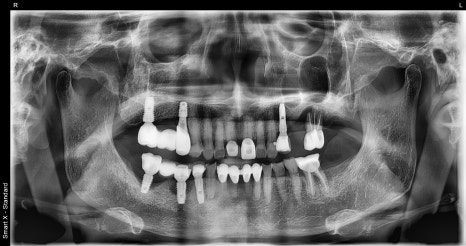

✅ 치료 후 사진

첫번째 사진: 치료 완료 후 파노라마 X-ray입니다. 새로 심은 #15 임플란트와 기존 #17 임플란트를 연결하여 어금니 기능을 회복했습니다.

두번째 사진: 치료 후 구강 내 모습입니다.

앞니 크라운과 어금니 임플란트 보철까지 완성된 상태로, 정확하게 맞물리며 식사 시 불편이 크게 줄어들었습니다.

임플란트는 안정적으로 유착되었고, 두 달 후 오른쪽 작은 어금니 임플란트 보철까지 마무리되었습니다.

씹는 기능이 회복되어 식사 시 불편함도 크게 줄었고, 보호자분께서도 “생각보다 수월하고 빨랐다”며 만족을 표하셨습니다 😊